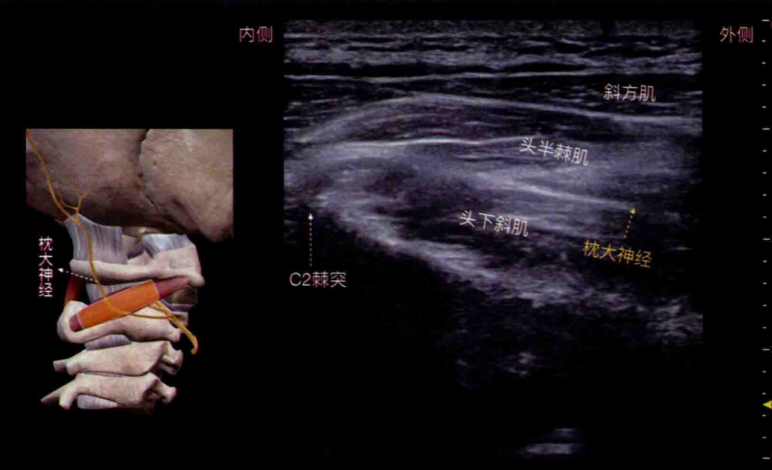

超声引导下神经阻滞治疗